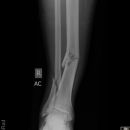

distaler Unterschenkelschaft

Es wurden keine Bilder gefunden.

Spiralfraktur Tibia